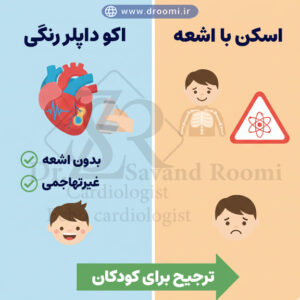

اینفوگرافیک مقایسهای که ایمن بودن اکو قلب بدون اشعه را در برابر روشهای تصویربرداری دارای اشعه نشان میدهد.

کاملاً غیرتهاجمی، بدون درد و بدون اشعه

یکی از برجستهترین مزایای اکو قلب رنگی اطفال این است که کاملاً غیرتهاجمی است. برخلاف روشهایی مانند سیتیاسکن یا آنژیوگرافی که ممکن است نیاز به تزریق ماده حاجب یا قرارگیری در معرض اشعه ایکس داشته باشند، اکو رنگی قلب بچهها تنها با استفاده از امواج صوتی فراصوت انجام میشود.

کودک هیچگونه درد، سوزش یا ناراحتی احساس نمیکند و معمولاً نیازی به بیحسی یا بیهوشی نیست. این ویژگی بهویژه برای والدینی که نگران عوارض روشهای تشخیصی بر فرزند کوچک خود هستند، آرامش خاطر زیادی به همراه دارد. در شیراز، پزشکان متخصص با تجربه فراوان، بررسی را در محیطی آرام و کودکدوست انجام میدهند تا تجربهای مثبت برای خانواده ایجاد شود.

ایمنی بالا حتی برای نوزادان تازه متولد شده

اکو قلب نوزادان یکی از ایمنترین روشهای تصویربرداری است و هیچ محدودیت سنی ندارد. حتی در ساعات یا روزهای اول پس از تولد، میتوان این بررسی را برای نوزادان نارس یا تازه متولد شده انجام داد بدون اینکه کوچکترین خطری برای سلامتی آنها ایجاد شود.

عدم استفاده از اشعه یونیزان (برخلاف رادیوگرافی یا سیتیاسکن) باعث میشود که اکو داپلر رنگی نوزادان هیچ ریسک بلندمدت مانند افزایش احتمال سرطان نداشته باشد. همچنین، این روش را میتوان بارها و در فواصل کوتاه تکرار کرد تا روند درمان یا بسته شدن خودبهخودی نقصهایی مانند VSD پیگیری شود. این ایمنی بالا، بهترین اکو کودکان شیراز را به گزینه اول پزشکان متخصص قلب اطفال تبدیل کرده است.